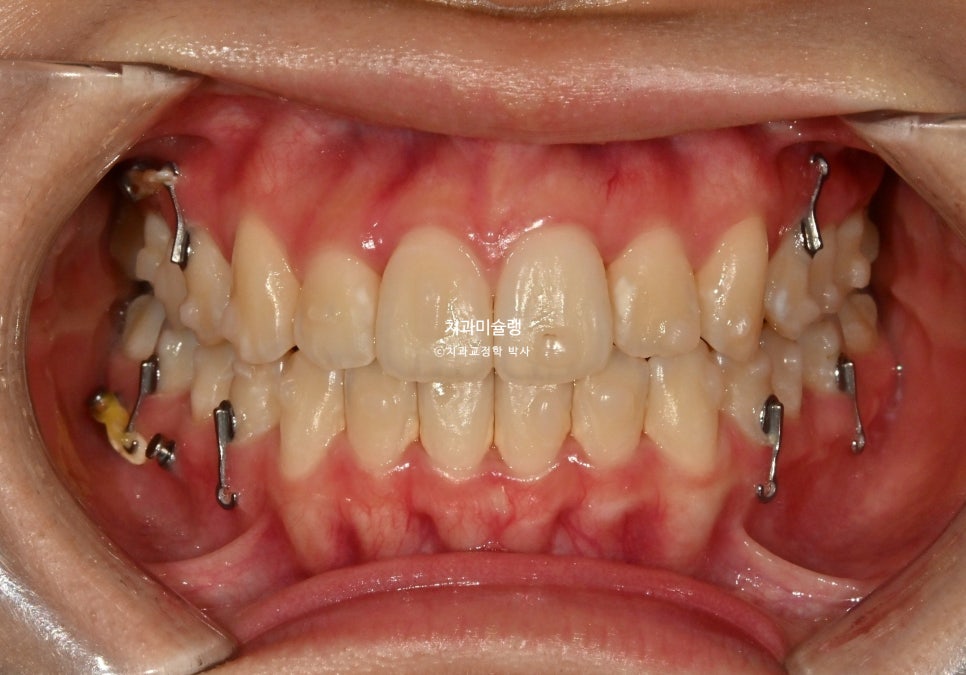

정확히 1년 2개월후, 장치를 다 낀 후 모습입니다. 중심선이나 배열 등은 좋습니다.

현재는 구치부 순차적 원심이동을 위해 좀더 예측가능성이 높은 방법을 씁니다만 이당시에는 이런 메카닉을 썼습니다. 환자분이 잘 껴주면 별 문제 없이 구치부 원심이동이 잘 되지만, 장치 끼는걸 소흘히 하면 치아의 회전 등의 문제가 생기기 때문이죠.

사랑니 공간으로 어금니들이 계획대로 2mm씩 후방이동 한것이 엑스레이로 확인됩니다.

어금니 교합 뜨는부분이 보여 교합 안정화를 위해 추가장치 제작에 들어갑니다.

추가장치는 12개가 나왔으며 3개월간 추가장치를 낀후 치료를 종료했습니다.